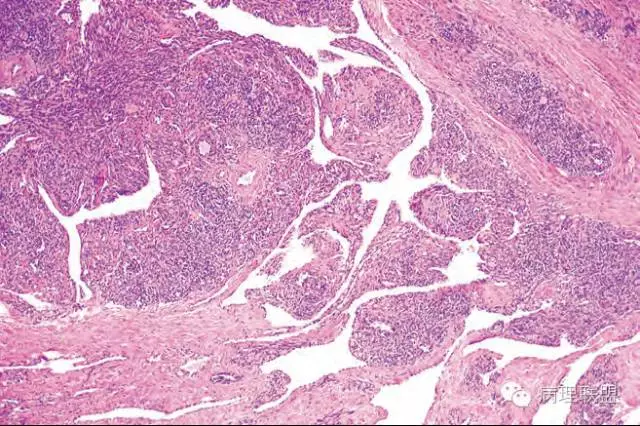

血管裂隙样,弯曲排列,似迷宫样,良性应该打不住,需往中间型考虑,请大咖们指点,软组织的重点应该放在良恶性的鉴别吧。

@南方医科大学病理梁莉 形态较符合复合性血管内皮瘤(composite hemangioendothelioma),属中间性血管性肿瘤。此肿瘤尽管多见于成人,也可发生于婴幼儿。

这例我们发的是卡波西样血管内皮细胞瘤,考虑如下:(1)新生儿,肢体肿物;(2)位置深,侵及皮下脂肪;(3)大多是裂隙状血管,也有少量吻合的血管网,细胞有异形,可见坏死

Kaposi型血管内皮瘤常有隐约小叶结构,梭形细胞束间有毛细血管,细胞核异型性和分裂活性一般不明显,常见梭形细胞束和圆形"肾小球样"实性细胞巢混合存在。

有些区域类似Kaposi肉瘤,如下图

而复合性血管内皮瘤则是由良性、中间性和恶性的成份组成,也是浸润性生长,常常侵犯皮下脂肪组织,此例细胞形态由梭形细胞、卵圆形细胞及上皮样细胞组成,形态可见良性区域、中间性区域及高分化血管肉瘤或上皮样血管肉瘤区域,因此,似乎复合性血管内皮瘤更妥。此类肿瘤可以发生于婴幼儿。当然与Kaposi型血管内皮瘤一样,同属中间性血管瘤,只是后者,若肿瘤体积大,可出现Kasabach-Merritt综合征。